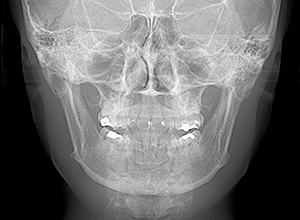

X-Ray

X-Ray所見

セファロ所見 下顎頭はやや後方に位置しているが、下顎は大きく力強い形態をしており下顎角は平均的であるのに対して、中顔面部は奥行きがなく前後的には後方に位置づいており劣位であるため、下顔面高は低く垂直的にはShort face様骨格形態を呈していた。

パノラマ所見 上顎両側8が存在していた。下顎臼歯は近心傾斜が認められた。